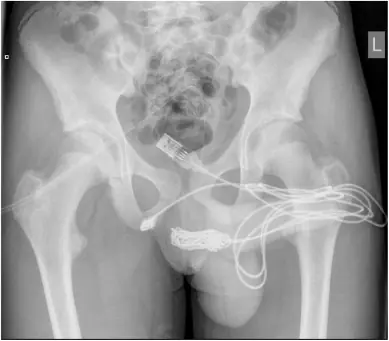

A teenage boy required medical attention after getting a USB cable stuck inside his penis.

As documented in Urology Case Reports in November 2021 (Volume 39), a 15-year-old boy from the United Kingdom was attempting to measure the inside of his penis with a cable as a form of "sexual experimentation".

However, the cable soon tangled and he became unable to remove it. With knots formed in the cable, the boy began to experience blood in his urine and was taken to the hospital by his mother.

In the report, the doctors discussed the bizarre incident and wrote: "The two distal ports of the USB wire were found to be protruding from the external urethral meatus whilst the middle part of the knotted wire remained within the urethra."

In an effort to extract the cable, surgeons cut lengthways into his bulbospongiosus muscle - an area between the genitals and the anus.

Doctors from University College Hospital London were present and managed to pull the knot through the incision and then cut it free from the rest of the cable.

Once the knot was removed, the remaining two pieces of the cord were pulled out of the opening of his penis. Fortunately, there were no complications in the teen's recovery and he was discharged from the hospital the next day.